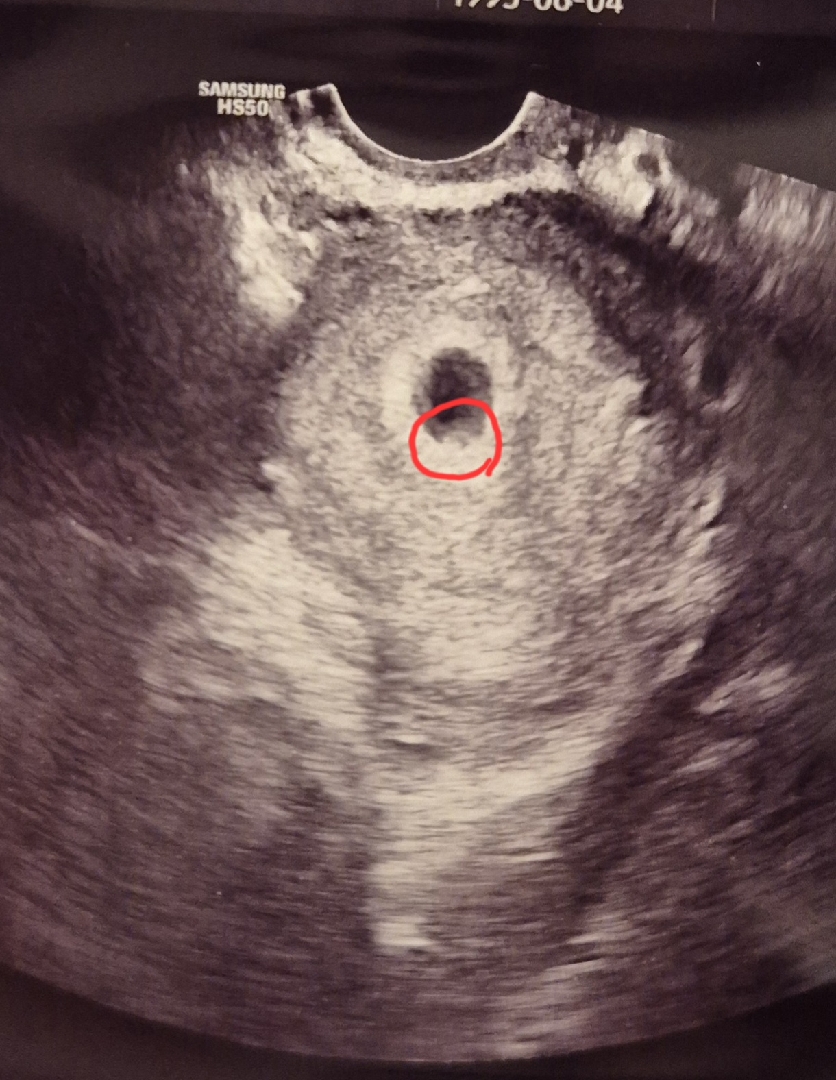

혹시 이게 난황일까요??

저번 주 토요일에 집들이 잘 하고 왔는데 선생님이 다 괜찮아서 그런 건지 5주라고만 알려 주시고 2주 뒤에 심장소리 들릴 때 보자고 진료가 끝나 버렸는데용...🥺 혹시 제가 표시한 저 부분이 난황이 맞을까요?? 못 여쭤봐서 넘 궁금하네요 !!! 🥹